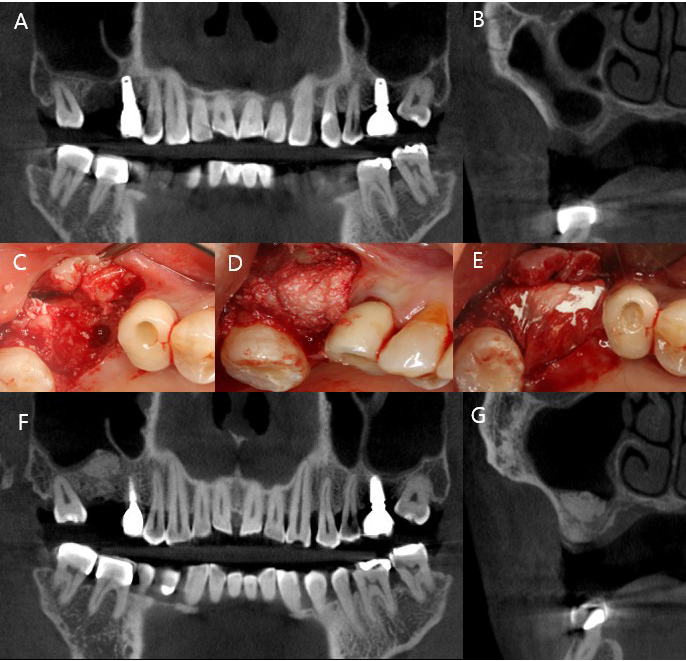

A 65-year-old male was referred to our clinic after experiencing two consecutive implant failures at the site of tooth 16 (Fédération Dentaire Internationale notation), which had been previously treated at a local clinic. The patient presented 3 months after removal of the second failed implant, having been informed at a local clinic that further implant placement was not possible due to insufficient bone volume. CBCT revealed near-complete loss of the sinus floor bone with a thick lateral wall (> 3 mm), rendering the lateral window approach less favorable and prompting the selection of transcrestal sinus elevation. Following full-thickness flap elevation, residual granulation tissue was thoroughly debrided. Tactile probing with an osteotome confirmed contact with the Schneiderian membrane and its integrity. Hydraulic sinus membrane elevation was performed using saline irrigation, followed by passive insertion of 0.5 g of deproteinized bovine bone mineral (Bio-Oss; Geistlich Pharma AG, Wolhusen, Switzerland) into the sinus cavity. Simultaneous GBR was performed in the extraction socket using a 250 mg block-type xenograft (Bio-Oss Collagen; Geistlich Pharma AG) and a ribose-crosslinked collagen membrane (Ossix Plus; Datum Dental Biotech, Israel). Primary closure was achieved using periosteal-releasing incisions and resorbable sutures. At 5 months, CBCT demonstrated substantial vertical bone gain of up to 13.1 mm. A dental implant (TS III, Ø5.0 × 8.5 mm; Osstem Implant, Seoul, Korea) was placed with adequate initial stability, and a healing abutment was connected at the time of surgery using a one-stage protocol. Prosthetic loading was initiated at 4 months postoperatively after confirming sufficient osseointegration with an implant stability quotient (ISQ) value of 80. The implant remained functional and complication-free during the 46-month follow-up period. The sequential clinical and radiographic findings of Case 1 are shown in Fig. 1.

Fig. 1

Representative case of crestal sinus elevation in an erratically healed extraction socket. (A, B) Preoperative cone-beam computed tomography (CBCT) showing severe crestal bone resorption and partial continuity of the extraction socket with the maxillary sinus cavity, (C–E) Intraoperative images after flap elevation and granulation tissue removal. Transcrestal sinus floor elevation with guided bone regeneration (GBR) was performed using deproteinized bovine bone mineral and an absorbable collagen membrane, (F, G) Five-month postoperative CBCT demonstrating hourglass-shaped bone formation with 13.1 mm vertical bone height gain.